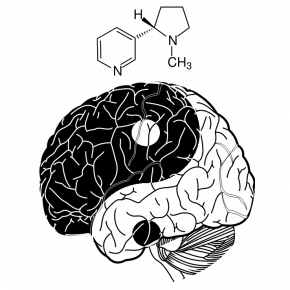

Cerveau connecté (1/4) : de quoi parle-t-on ?